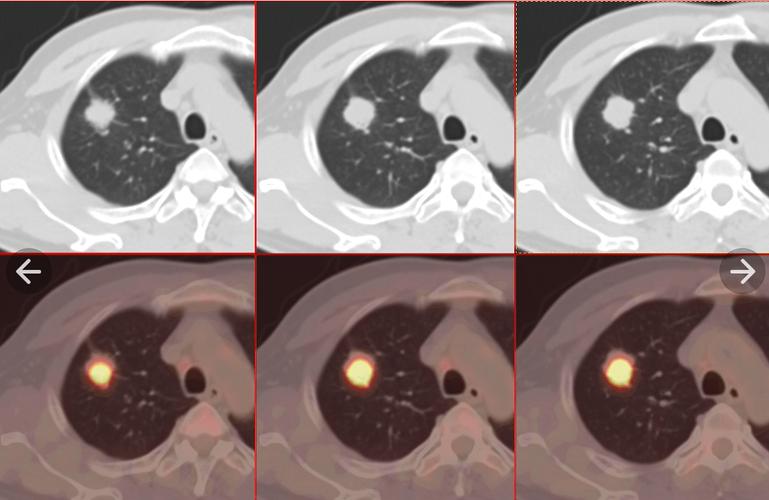

这是考试中的关键内容,同时也是难点所在。考生需仔细观察CT图像,对病变的具体位置、形状、密度等特性进行精确识别,同时还要对其可能的致病原因进行深入分析。以肺部结节为例,对其良性或恶性的判断,必须综合考虑结节的大小、边缘的清晰度、密度等多种因素。

图像分析要求具备深厚的临床知识及出色的观察能力。在平日里,应广泛接触各类病例影像资料,深入探究不同病变间的特点与区别。面对考试中的复杂图像,需保持冷静,细致分析,以免出现漏诊或误诊的情况。